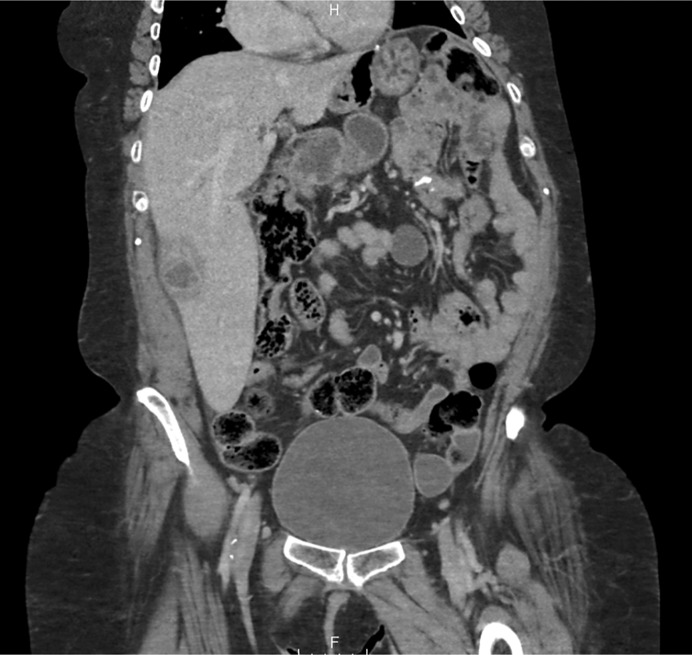

Introduction: Aseptic hepatic abscesses are a highly uncommon phenomenon and even more rare in the spectrum of extraintestinal manifestations of inflammatory bowel disease. Part of the spectrum of "neutrophilic disease," both the pathogenesis and the optimal management of these aseptic abscesses remain unclear. In the context of inflammatory bowel disease, sometimes these abscesses appear despite normal endoscopic findings.

Case presentation: We describe a highly uncommon case of aseptic hepatic abscess formation in a patient with inflammatory bowel disease.

Abstract Image